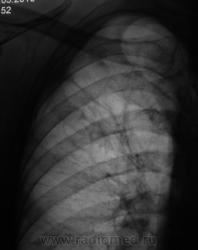

Какая-то фиброзно-кистозная дегенерация легочной ткани в/д правого л-го. Вероятно, приобретенная.

Остаточные буллёзно-фиброзные изменения излеченного туберкулеза легких?